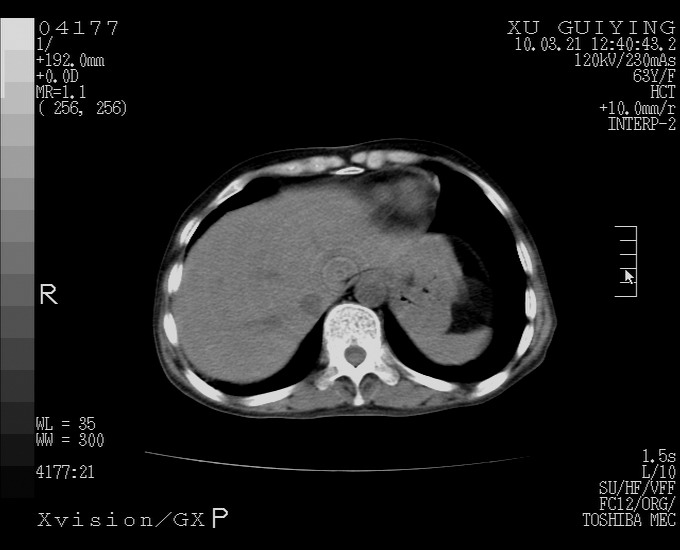

怎么没有增强呢?胆囊那么大,密度有些高啊。

慢性胆囊炎,胆囊占位不排除,建议增强或彩超。

考虑胆囊炎 不除外泥沙样结石

胆囊体积增大,胃窦壁增厚

胆囊体积增大

胆囊体积增大,密度不均匀,结石不除外;胃壁增厚,考虑胃癌,建议增强。

胆囊体积增大 ,建议超声检查。

胆囊体积增大,密度增高,较均匀,外缘也较光滑,应考虑胆囊炎。因为胃未充盈,不好说壁增厚。肝左叶及脾门处见低密度灶,有可能是血管瘤,不排除囊肿。建议超声检查或强化。

胆囊增大,原因待查。

这就是江湖人称的“内科黄疸”, 肝内胆汁淤积症(ic)?